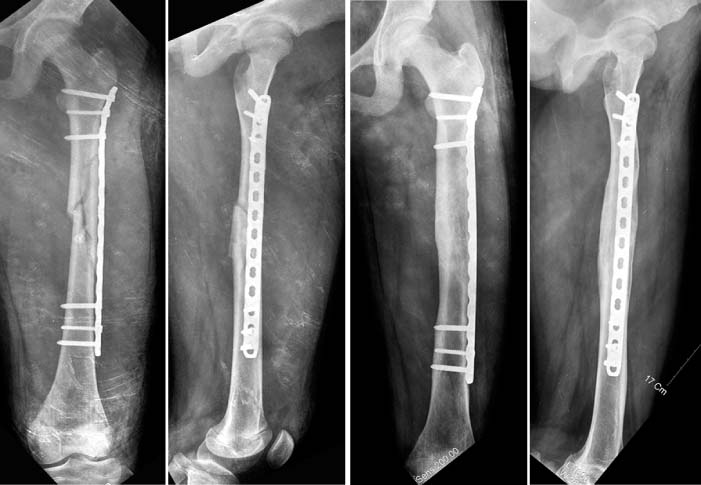

Fig. 7

A proximal femoral fracture in 7 years-old boy. In this fracture, the proximal fragment usually abducts and rotated externally. It makes the reduction very difficult. In the past, open reduction with the plate was commonly used.

Fig. 8

With flexible nails, the reduction was achieved. Then, the plate was fixed in the MIPO method.